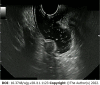

Rectal neuroendocrine neoplasms (r-NENs) are considered among the most frequent digestive NENs, together with small bowel NENs. Their incidence has increased over the past few years, and this is probably due to the widespread use of endoscopic screening for colorectal cancer and the advanced endoscopic procedures available nowadays. According to the current European Neuroendocrine Tumor Society (ENETS) guidelines, well-differentiated r-NENs smaller than 10 mm should be endoscopically removed in view of their low risk of local and distant invasion. R-NENs larger than 20 mm are candidates for surgical resection because of their high risk of distant spreading and the involvement of the muscularis propria. There is an area of uncertainty regarding tumors between 10 and 20 mm, in which the metastatic risk is intermediate and the endoscopic treatment can be challenging. Once removed, the indications for surveillance are scarce and poorly codified by international guidelines, therefore in this paper, a possible algorithm is proposed.